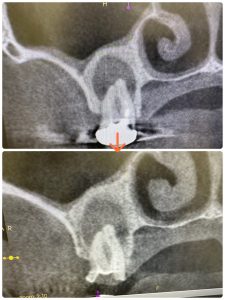

患者さんが持参してきた総合病院口腔外科からの報告書

順調に骨化傾向にある、咬合痛もなし